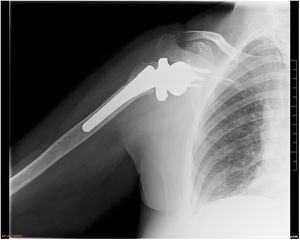

Postoperatoriamente, se realizaron controles al mes, 3 meses, 6 meses y al año. Dos cirujanos independientes fueron los encargados de valorar inicialmente la correcta consolidación de las tuberosidades, y posteriormente era corroborado por un cirujano sénior en las 2 proyecciones radiográficas (AP verdadera y axial) a todos los pacientes que decidieron participar y llevaban como mÃnimo un año de seguimiento. Se categorizó como consolidación no anatómica (grupo 2) cuando existÃa: no unión, malunión u osteólisis de las tuberosidades. Más especÃficamente, dentro del subgrupo se incluyeron: los pacientes con ausencia de tuberosidad, una separación>1cm del fragmento a la diáfisis humeral, o que la tuberosidad se encontrase por encima de la bandeja humeral (figs. 1 y 2). El estudio fue aprobado por el Comité Ético de Investigación.

En este estudio, se obtuvo una baja tasa de consolidación de las tuberosidades (54%), ligeramente inferior a la descrita en la literatura (64-84%)16–23; solo Chun et al.24 reportan una tasa de consolidación inferior (34%)24. Esta diferencia, según nuestra hipótesis inicial, puede ser debida al diseño protésico utilizado: diseño lateralizado con bandeja de diámetro grande, siendo el tamaño más pequeño disponible el de 44mm. Este gran diámetro puede dificultar el cierre de las tuberosidades, quedando estas con excesiva tensión y comprometiendo asà la consolidación cuando se compara con los otros diseños protésicos (fig. 3). Esta diferencia de tamaño en la bandeja es notable si tenemos en cuenta el incremento de área de superficie que supone. Por ejemplo, la diferencia de superficie (cm2) entre la bandeja de 32mm de Humelock Reversed® (área de superficie 8cm2), de Fx Shoulder Solutions, y la bandeja de 44mm (área de superficie 15,2cm2) modelo Comprehensive® Reverse Shoulder System, de Zimmer Biomet, corresponde a un aumento de un 90% (tabla 4).